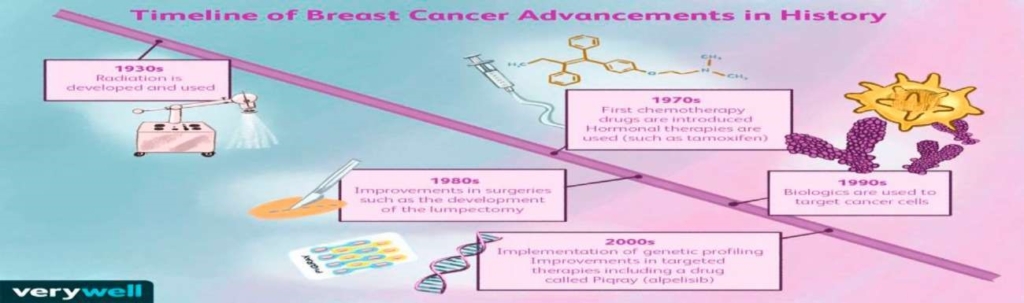

History of Breast Cancer Treatment:

Breast cancer treatment has gradually evolved over the years. In recent times, newer developments have significantly improved the overall outcome of most patients who present early. Even for patients who present with advanced disease, options for treatment and control of disease continue to improve. History dates back to the 19th century when major landmarks in the treatment of breast cancer begun to unfold. Treatment of breast cancer however dates back to ancient times.

Evolution of newer cancer treatments (Systemic therapy):

Some major landmarks include performing of the first radical mastectomy, mammography, use of radioactive substances and later in the twentieth century, development of various forms of treatments which enter the blood stream and travel to every part of the body. This includes chemotherapy and hormonal therapeutic drugs which when combined with surgery, effectively treat and manage breast cancer. With time, more recent drugs have been developed, which target the proteins that breast cancer cells use to grow, spread and live longer.